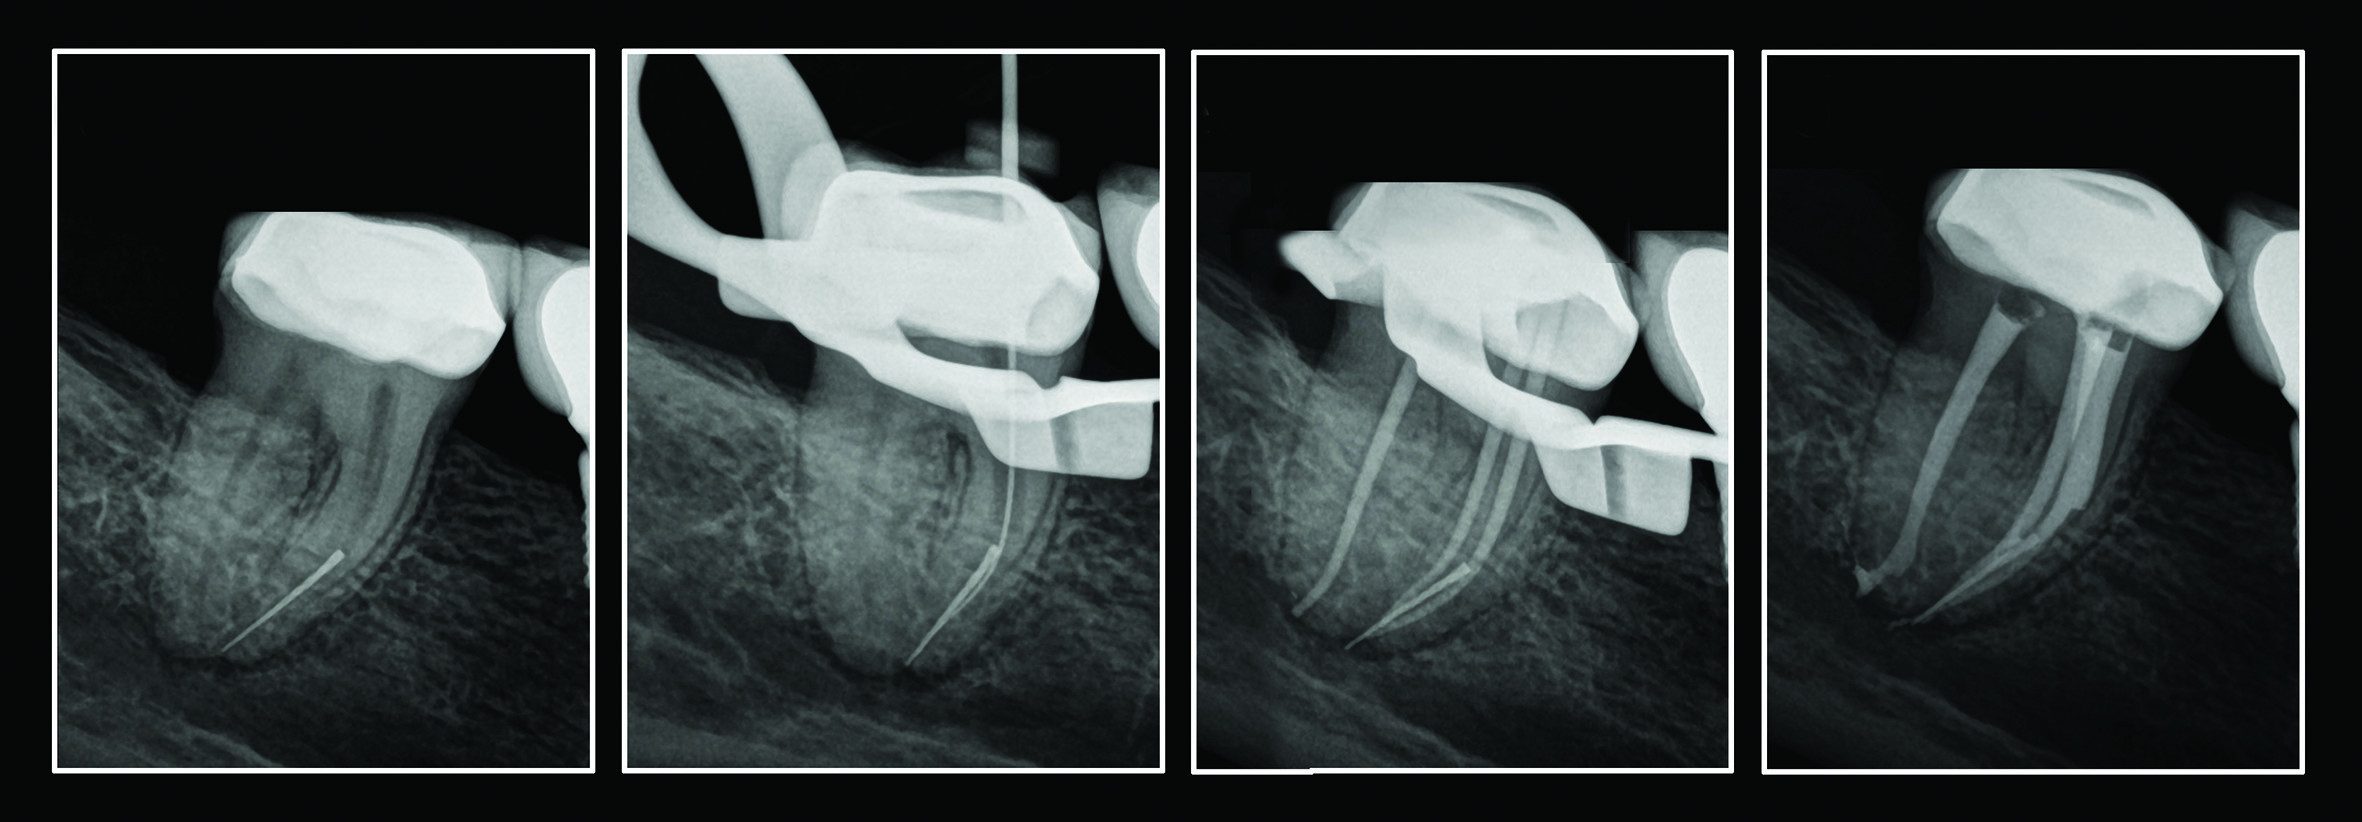

Peet J van der Vyver, Martin Vorster and Ove A Peters explore the use of the Trunatomy system in conventional root canal treatment and illustrates the use of the instruments in complex and challenging endodontic cases.

To describe the use of Trunatomy, a new single-file rotary file system, using various clinical case studies.